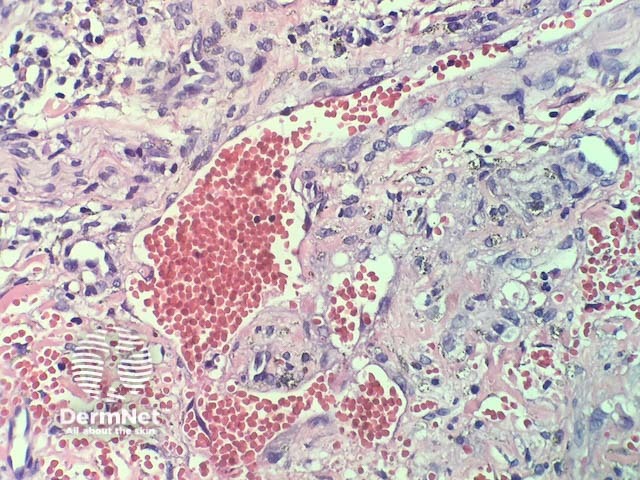

In verrucous haemangioma, the histopathology shows irregular papillomatosis, acanthosis and hyperkeratosis of the epidermis. The dermis shows multiple, thin-walled, dilated blood-filled spaces. Intravascular thrombosis with recanalisation and haemorrhage can be seen (figures 1–5).

Figure 2